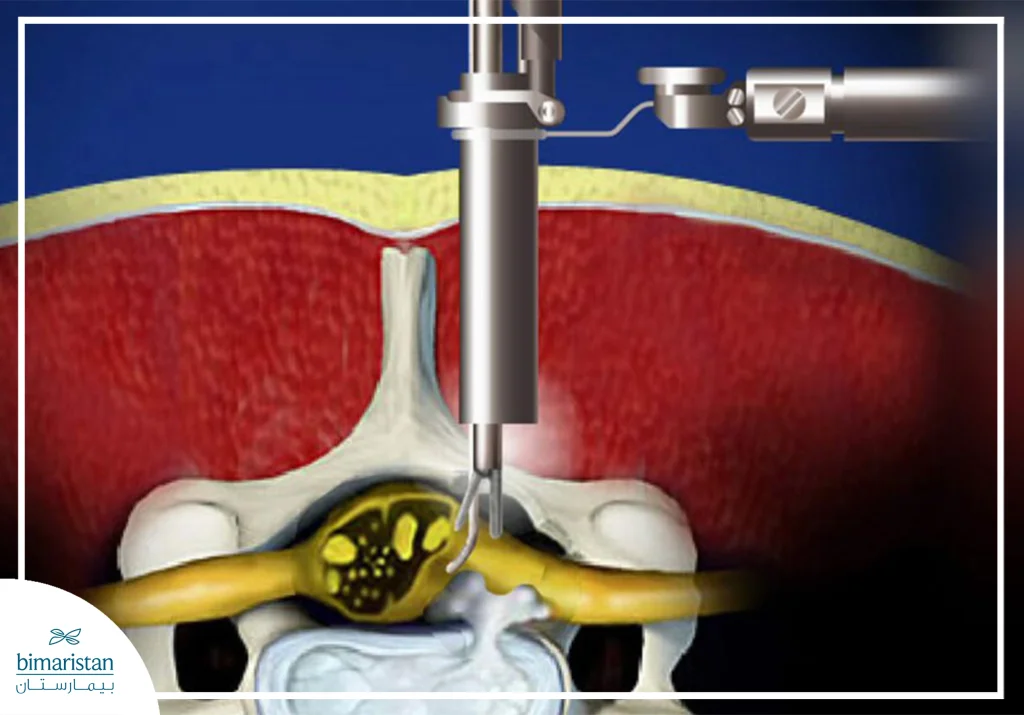

The procedure begins with anesthesia, as it is usually performed under general anesthesia. The patient is placed on his stomach in a way that allows the wound to safely reach the lumbar or cervical vertebrae, depending on the location of the herniation. The surgeon makes a small incision, usually between 1.5 and 3 cm above the affected vertebra, and at this stage, the surgical microscope is used to magnify the vision with high precision.

After the incision is made, the muscles are gently moved away without cutting them (to minimize pain and recovery time) to reach the location of the pinched nerve. The area is carefully assessed, then using precise instruments, the surgeon removes only the herniated part of the cartilage that is pressing on the nerve, leaving the rest of the disc intact to keep the spine stable, and finally, the tissue is put back in place. The incision is usually closed with only one or two stitches, and the patient is transferred to the recovery room and then to their hospital room.